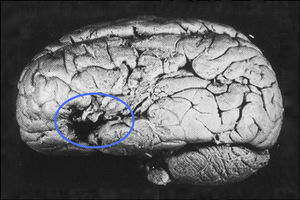

Paul Broca (1824–1880) verschaffte der Lokalisationstheorie wieder Gehör, als er 1861 eine Autopsie an einem Patienten durchführte („Monsieur Tan“), der Sprache zwar noch verstehen, sich aber nicht mehr selbst sprachlich äußern konnte. Broca fand eine klar umgrenzte Schädigung in einem Bereich des linken Frontallappens, der bis heute Broca-Areal heißt, und konnte den Sitz des Sprachvermögens somit präziser angeben als zuvor. 1865 folgte die Einsicht, dass die linke Hirnhälfte für das Sprechen eine besondere Rolle spielt. Marc Dax (1771–1837) hatte diese Vermutung bereits 1836 geäußert und sein Sohn Gustave Dax hatte in einem Manuskript auf diese Entdeckung hingewiesen, das wenige Tage bevor Broca an die Öffentlichkeit trat, bei der Pariser Académie de Médecine eingegangen war. Ob Broca die Forschung von Dax kannte, als er seinen eigenen Artikel verfasste, gilt als ungesichert.[28] Da bei einigen Patienten Fähigkeiten nach einer Hirnschädigung mit der Zeit zurückkehrten, postulierte Broca bereits Mechanismen der kortikalen Plastizität, aufgrund derer Hirnareale ihnen ursprünglich fremde Aufgaben übernehmen können, und empfahl eine unterstützende Sprachtherapie für Schlaganfallpatienten.